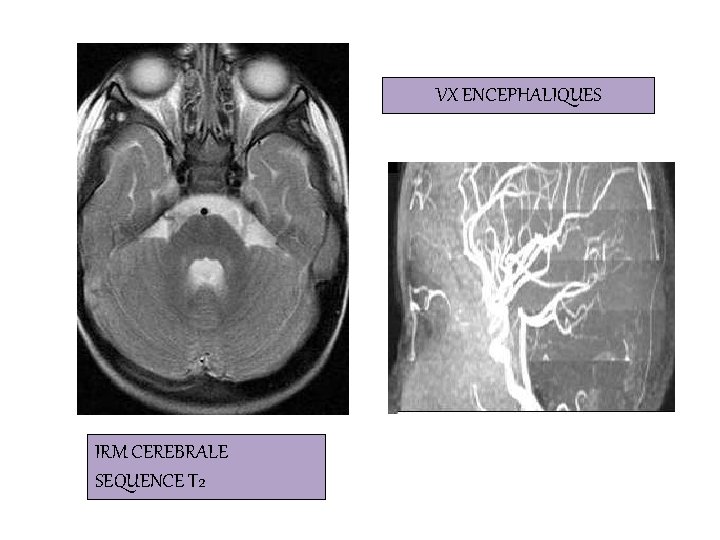

VX ENCEPHALIQUES IRM CEREBRALE SEQUENCE T 2

IRM CEREBRALE / MEDULLAIRE/ CEREBRO-MEDULLAIRE Bonne exploration encéphalique, médullaire et des nerfs crâniens IRM CARDIAQUE -Technique de référence pour l’évaluation de la fonction cardiaque. - Etude morphologique et dynamique du cœur et des gros vaisseaux. -Antenne cardiaque: indispensable mais coûteuse, - Service hyperspécialisé avec cardiologue et radiologue ANGIO IRM ou ARM - Destinée à l’exploration du territoire vasculaire. -En contraste spontané time of fligt : 2 D TOF ou 3 D TOF -Injection de gadolinium (ARM)